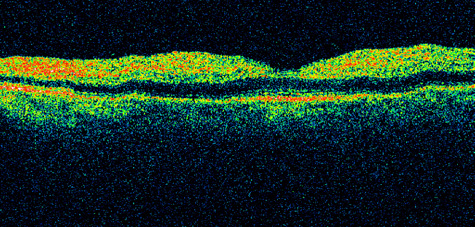

The clinical picture is typically striking. Patients present with a sudden painless loss of vision. The appearance of a cherry-red spot in the fundus is characteristic (Fig. 1).2 The cherry-red spot appears because soon after obstruction of the blood flow to the inner retina, the normally transparent retina becomes opaque and blocks the brownish-red color from the underlying choroid, which is still supplied by blood. Because the retina overlying the foveola is relatively thin, however, the normal color of the choroid is still visible in this area.3,4 Although characteristic, the cherry-red spot is not pathognomonic for central retina artery obstruction.5 Sometimes the characteristic cherry-red spot does not develop; there may be only a slight accentuation of the brownish-red color in the foveola.4 It is not known how long it takes this cherry-red spot to appear, but in a primate model, it has appeared as early as 30 minutes after obstruction.6 An afferent pupil defect is usually present.2

Fig. 1. A: Acute central retinal artery obstruction with a cherry-red spot. B and C: Intravenous fluorescein angiography. There is a delay of dye appearance in the central retinal artery, and when it does appear, it does not fill the arteries completely. D: Ocular coherence tomography (OCT) at the time of occlusion showing the increase in retinal thickness and reflectivity of the inner layers of the retina. E: Seven months later there is significant optic atrophy(G), and the OCT (F) shown now has marked thinning of the retina.

With time, the retinal opacity diminishes, generally leaving an optic nerve that is atrophic (Fig. 1). Frequently, thinned retinal arteries and veins also remain.7,8 No foveolar light reflex is evident, and a finely pigmented appearance of the macula is typical.7 In some cases, arterial collaterals develop at the optic disc.9–11 Rarely, anatomoses that exist between the central retinal artery and the ciliary arteries become visible as preretinal loops (Nettleship collaterals) after an occlusion at the edge of the disc.12,13,378In approximately 20% of patients, an embolus is evident somewhere in the arterial system.14 Emboli are discussed later.

Intravenous fluorescein angiography is useful in showing the details of the abnormal circulation of a central retinal artery obstruction (Fig. 1). The principal abnormality is the delay in the appearance of the dye in the central retinal artery and its branches.2 Rather than the central retinal artery and its branches filling rapidly, considerable time may elapse before the entire arterial system is filled.15 The filling of the retinal arteries is often abnormal, with the fluorescein partially filling an artery (a dye front) or hugging the vessel wall, as in normal venous filling.15

Optic coherence tomography (OCT) of an acute central retinal artery occlusion shows a slight increase in the thickening of the retina and reflectivity of the inner layers of the retina that correspond to the opacity seen clinically (Fig. 1).409 With time, the disc becomes atrophic and the retina thinner.